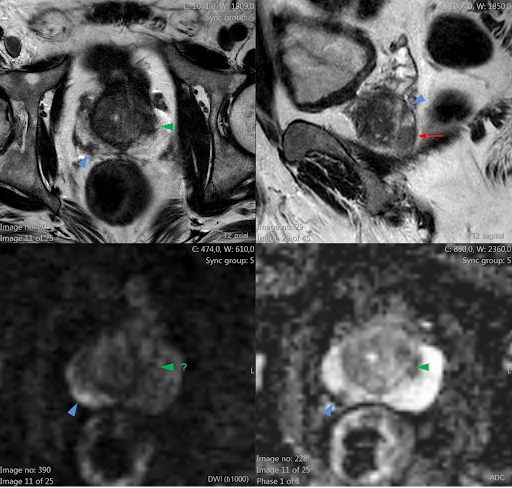

Lesões nodulares prostáticas (setas) com hipossinal T2 (imagens 1 e 2) e restrição à difusão (imagens 3 e 4), sem extensão extracapsular.

PI-RADS 4 – Alta probabilidade de neoplasia clinicamente significante.